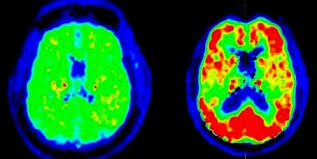

there is a test that may give me the definitive answer

its the beta amyloid pet scan

ive had one already and will have another next year with the

study that im in

the (adni) alzheimers disease neuroimaging initiative

but they dont give me the results

it would be the piece of the puzzle that im missing

the test is now available commercially in some areas

the amyvid pet scan

they inject a radioactive substance that attaches itself to

any anyloid deposited in the brain

if amyloid is present it will show up as red highlighted areas

if i have no amyloid present then there is a good chance that

my symptoms are not from alzheimers

not definite but as definite as you can be

if amyloid is present that doesnt mean you have alzheimers but

it implies that you might